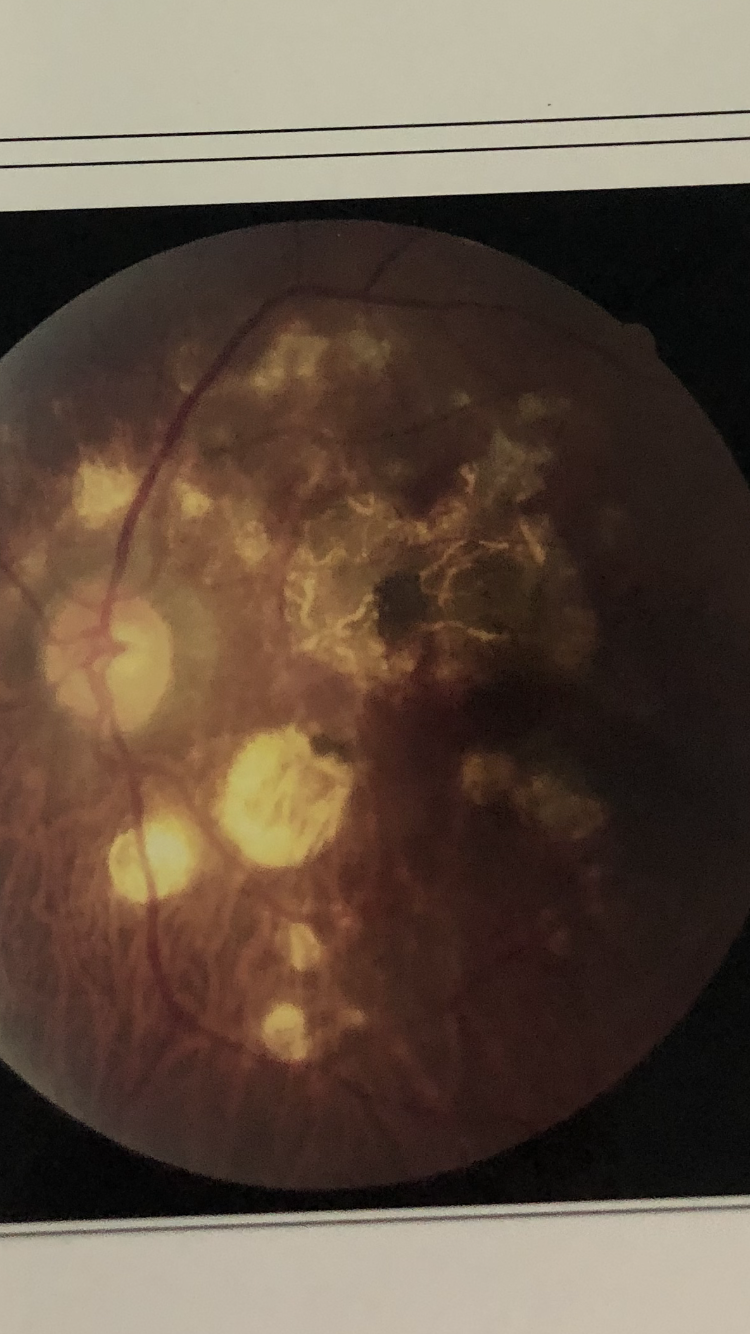

很多眼底疾病,比如黄斑裂孔,黄斑前膜,糖尿病性视网膜病变、玻璃体积血、孔源性视网膜脱离等,都需要进行眼底手术治疗。眼底手术是眼科手术当中最为精细和挑战的手术了,所以有人形容白内障手术是浅水潜水,而眼底手术是深水潜水。但是眼底手术康复后很多,需要1-2个月长期使用各类眼药水进行术后对症治疗,往往会造成眼部的不适感,比如干涩、异物感、疲劳、眼睛容易充血。很多都是术后干眼症、长期使用各类眼药水的表现。很多患者往往还沉浸在恢复光明的喜悦当中,往往忽视了术后干眼症的情况。而有的患者对这样的情况重视不够,或者自己主观臆断认为需要继续滴用抗生素激素眼药水,这样长此以往,反而会使眼部的不适感加重,甚至造成药物毒性的角膜病变。